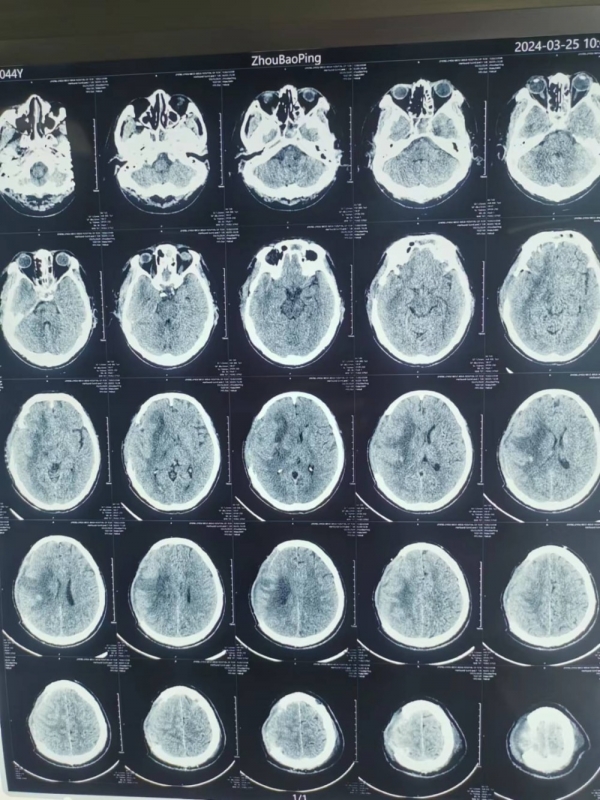

術(shù)后,評估、討論、制定方案·····抱著必須讓患者活下來,盡力達到最佳救治效果的目標(biāo),楊主任團隊積極展開一系列專業(yè)治療,周先生還較年輕,是家里的頂梁柱,家屬期盼很高,但他腦出血量又較大,術(shù)后“腦腫脹”風(fēng)險極高,主管醫(yī)師胡升陽頂著壓力,持續(xù)監(jiān)測顱內(nèi)壓變化,并詳細記錄數(shù)值變化規(guī)律,調(diào)整治療藥物用量;每日見到患者家屬“期盼的眼神”,ICU醫(yī)護人員都身同感受,時刻盡己所能,助力患者病情恢復(fù)。

“功夫不負有心人”,術(shù)后第6天,周先生復(fù)查結(jié)果顱內(nèi)水腫較前明顯好轉(zhuǎn)。但暫時的好轉(zhuǎn)并不意味著患者已經(jīng)“轉(zhuǎn)危為安”,術(shù)后各種并發(fā)癥逐漸出現(xiàn),“肺部感染”,“臟器功能不全”,持續(xù)威脅患者生命,而這其中任何一種并發(fā)癥對患者都有致命的危險。巨大的壓力再次壓到了醫(yī)生們肩上,討論、評估、制定方案、修改、再討論ICU醫(yī)護們?nèi)找岳^夜將救治方案得到最優(yōu)。